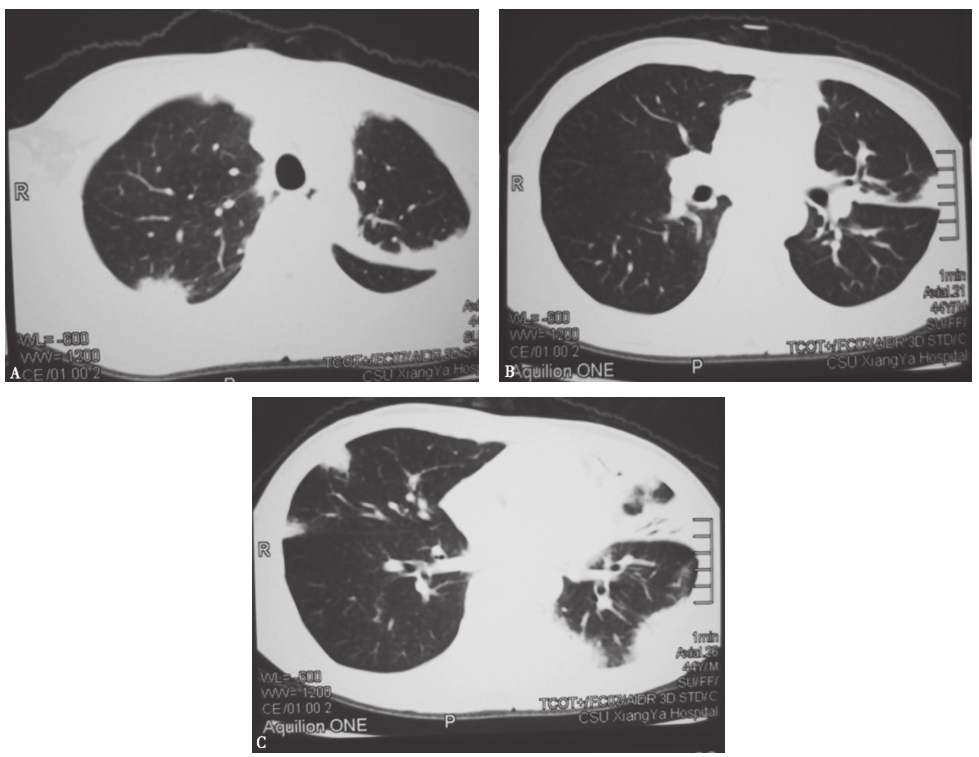

2013年1月4日查胸部CT,见双肺多发实变影,其间可见支气管充气征,伴左侧少量胸腔积液(图1)。

图1胸部CT表现(2013-01-04)